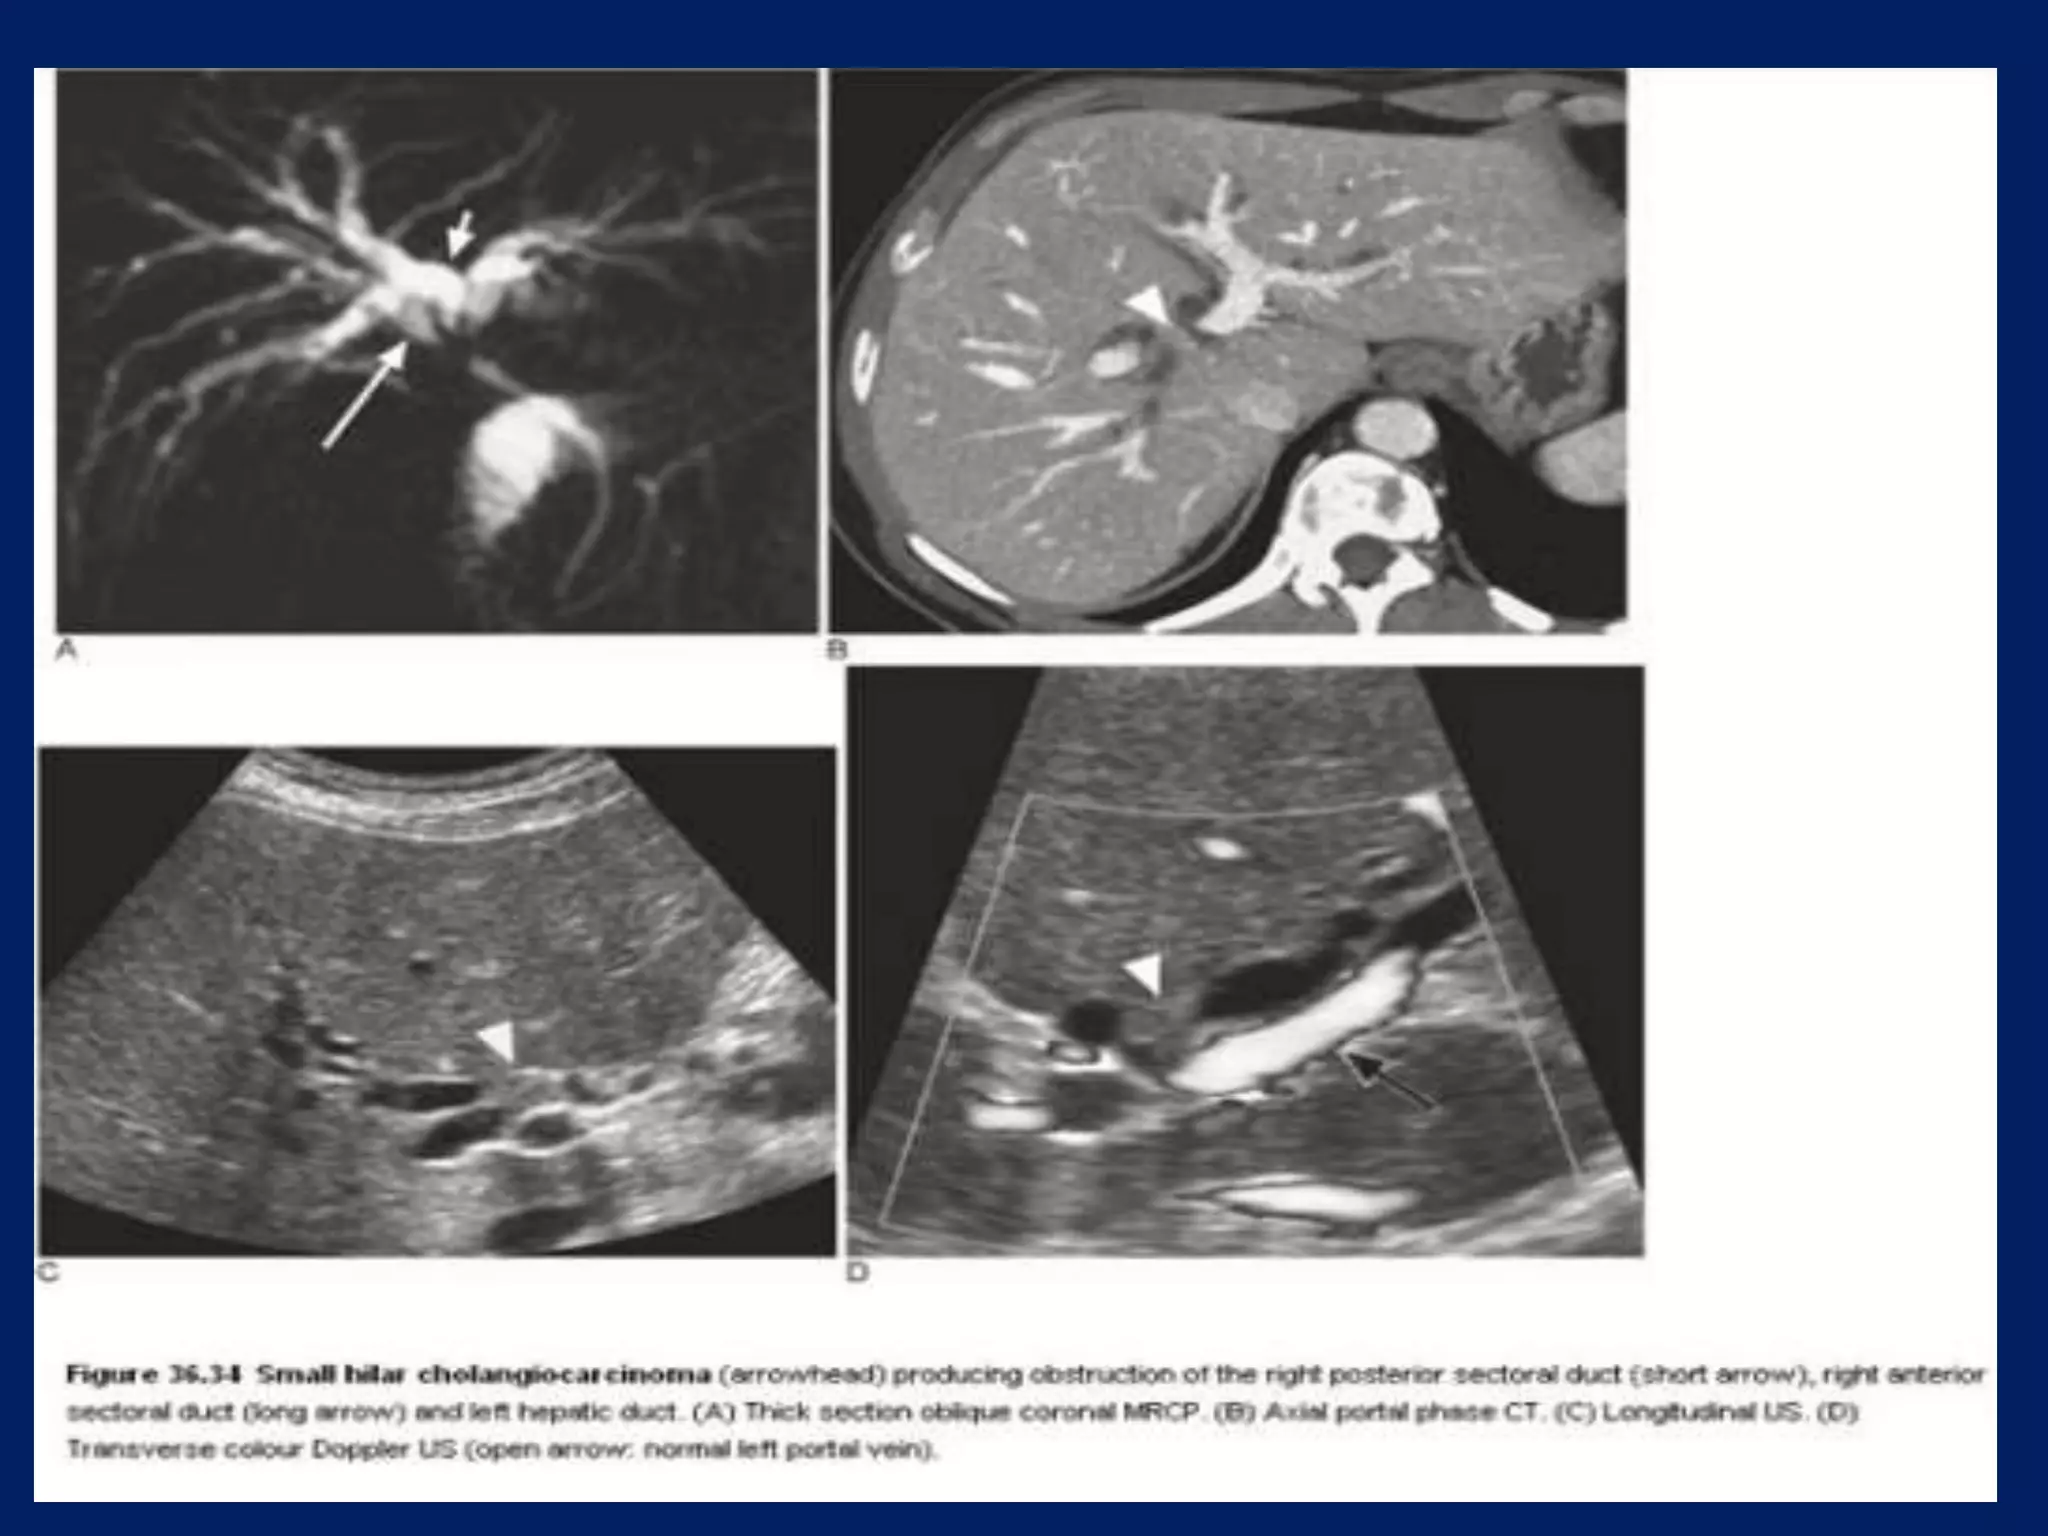

This document discusses imaging techniques for evaluating the biliary system. It covers common bile duct stones and Mirizzi's syndrome, which involves compression of the common bile duct by gallstones. It also mentions biliary cystadenoma, a type of cyst forming in the bile ducts or gallbladder.